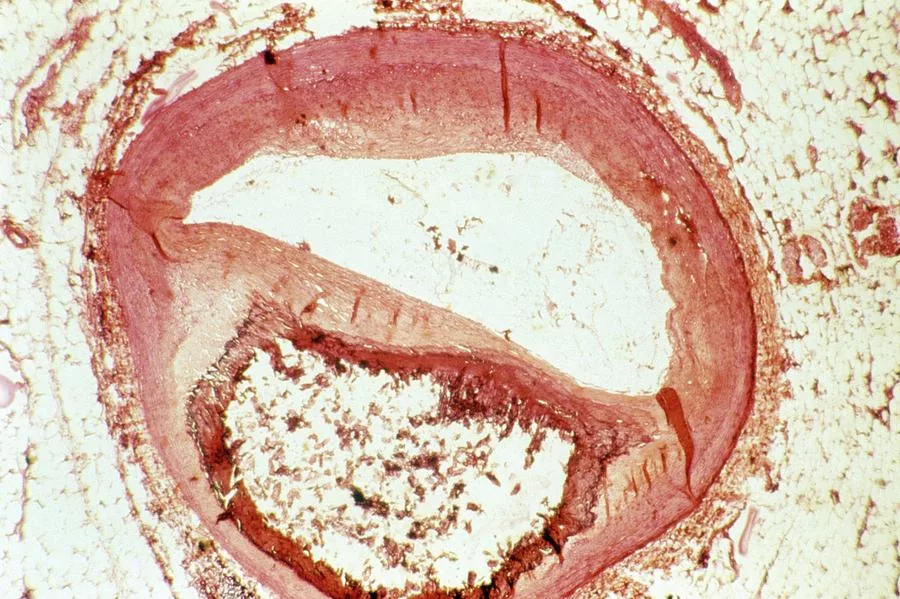

Женщина 73 лет с тяжелым атеросклерозом всех основных сосудистых бассейнов - поражены коронарные артерии, аорта, нижние конечности и - более всего - артерии, кровоснабжающие мозг. Откуда у нее такое злокачественное течение атеросклероза? Для этого, как это обычно бывает, есть причины. Во-первых, семейная гиперхолестеринемия - я наблюдал три поколения женщин этой семьи, и у всех высоченный уровень холестерина ЛПНП ("так называемого "плохого ХС"). У дочери 9,6 ммоль/л, у внучки - 10,4 ммоль/л. У бабушки определить, какой он без лечения, было невозможно, так как старые результаты анализов за давностью лет уже утрачены, а те, что сделаны в последние годы - все выполнены на фоне лечения. Во-вторых, у женщины имеется сахарный диабет 2 типа, который обычно резко ускоряет развитие атеросклероза и придает атеросклеротическим поражениям диффузный характер. В-третьих, в этой семье еще одна генетическая проблема - гиперлипопротеинемия (а) - читается "гиперлипопротеинемия а малое". Это независимы

В итоге сочетания всех этих проблем у женщины уже в среднем возрасте развился ишемический инсульт (в 56 лет). Спустя 3 года развился второй инсульт. К счастью, оба инсульта не были тяжелыми, поэтому на момент моей встречи с пациенткой она была довольно сохранной, передвигалась своими ногами, сохраняла способность к самообслуживанию и нормально владела речью. Артерии, кровоснабжающие мозг, были серьезно повреждены атеросклерозом, и 11 лет назад была выполнена каротидная эндартерэктомия из правой внутренней сонной артерии, т.к. там имелась почти полная окклюзия (закрытие просвета). В других артериях тоже имелись существенные поражения: стеноз левой внутренней сонной артерии (40%), стеноз правой общей сонной артерии 50% и левой общей сонной артерии 40%.

В 2021 году она перенесла нижне-боковой инфаркт миокарда, выполнено стентирование огибающей артерии. Поскольку при коронароангиографии были выявлены значимые стенозы и других коронарных артерий, в том числе проксимального отдела передней нисходящей, пациентка была проконсультирована у кардиохирурга, но тот счел выполнение коронарного шунтирования невозможным или по крайней мере очень рискованным, учитывая выраженный кальциноз аорты («фарфоровая аорта») и коронарных артерий, нешунтабельное дистальное русло передней нисходящей артерии (то самое диффузное поражение, когда артерии поражаются не в отдельных участках стенозов, а на всём протяжении).